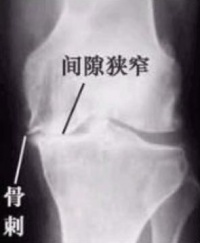

骨刺,学术名词为骨 ( Bone Spur ),不是一个医学上确当的名词,因为它既非完全由骨构成,也不尖锐如刺。医学上的正确名称应该是骨疣。骨刺是关节因种种原因造成软骨的磨损、破坏,并促成骨头本身的修补、硬化与增生,是一种自然的老化现象,一般长骨刺就表示此人的脊椎进入老化阶段。然而, 骨刺并非老人家的专利,由于工作型态改变,许多人必须久坐、久站,若是加上姿势不正确,很容易年纪轻轻就使脊椎提早发生退化现象,而诱发骨刺的发生。

骨疣是脊椎退化过程中所伴随的一种现象,随着年龄的增长,人体的脊椎构造也会跟着退化,当骨头与软组织接壤的地方因长期承受压力、拉力、损伤,造成脊椎与 脊椎间的软骨渐渐失去水分与弹性,致使骨骼出现退化性改变,这种骨骼退化性改变就会导致骨质增生,而形

成骨疣。另外,反复活动或不适当的运动,也常会使关 节部位的骨骼及软组织过度磨损,而长出骨刺。

骨疣不见得一定会产生症状,要看是否有压迫到神经根或是脊椎,如果没有的话就不会有什么让人不适的症状产生。相反的,如果骨刺刚好压迫到附近的神经根或是压迫到脊椎,就可能会有身体僵硬不能灵活弯身、疼痛、红肿麻痹、关节变形、肌肉无力等症状。

人体的关节活动久了也容易发生病变。骨疣一般好发于活动较频仍的关节,由于这些关节长时间反复使用,因此很容易发生磨损与退化的现象。而身体容易诱发骨刺生长的地方包括颈椎腰椎膝关节、脚跟,另外,手指跟手肘也是骨刺容易发生的部位。